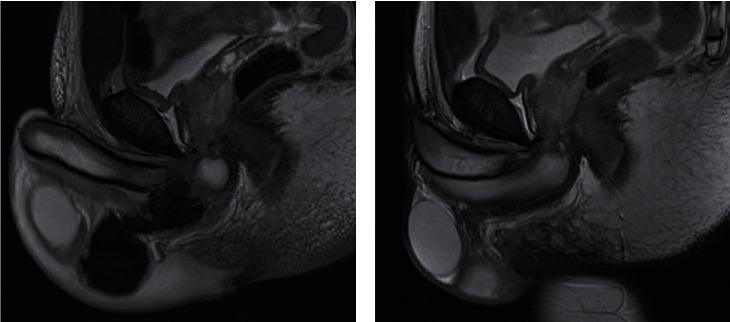

Penile fracture is a urological emergency, and surgery is usually recommended to prevent complications. However, proximal locations are scarce and not well investigated. We present two rare penile fractures involving the proximal corpora cavernosa with an original conservative strategy to manage this clinical presentation. Twenty-five- and thirty-eight-year-old men with no previous medical history were admitted to the emergency room for penile trauma during sexual intercourse a few months apart. Both presented with "butterfly pattern" ecchymosis with a palpable hematoma on the perineum. They had no hematuria or voiding dysfunction. Ultrasound found a hematoma and a tear of the proximal corpus cavernosum for the younger one. Then, an MRI confirmed a longitudinal fracture of the right corpus cavernosum for the first patient and left for the second, without urethral injury. In agreement with the patients facing this atypical presentation, we proposed a conservative treatment with analgesics, monitoring, and advice to stop sexual activity for three weeks. After six weeks and four weeks, respectively, we performed a clinical evaluation and a second MRI that found no residual tear or hematoma. The IIEF-5 questionnaire was 24/25 and 25/25. The patients were clinically symptom-free at 8 and 11 months of follow-up. Extreme proximal fracture of the corpus cavernosum can be managed conservatively in selected situations. MRI is useful for decision-making by confirming the diagnosis and location to avoid surgery.

阴茎骨折是一种泌尿外科急症,通常建议手术以预防并发症。然而,阴茎近端骨折的情况少见且研究不足。我们报告两例罕见的阴茎近端海绵体骨折,并采用了一种全新的保守策略来处理这种临床表现。两名分别为25岁和38岁且无既往病史的男性,在相隔数月的性交过程中发生阴茎外伤后被送入急诊室。两人均表现为“蝴蝶样”瘀斑,会阴部可触及血肿。他们均无血尿或排尿功能障碍。超声检查发现较年轻患者的近端海绵体有血肿和撕裂。随后,磁共振成像(MRI)证实首例患者右侧海绵体纵向骨折,第二例患者左侧海绵体纵向骨折,均无尿道损伤。经与面临这种非典型表现的患者协商,我们提出采用镇痛药、监测以及建议停止性活动三周的保守治疗方案。分别在六周和四周后,我们进行了临床评估及第二次MRI检查,结果未发现残留撕裂或血肿。国际勃起功能指数-5(IIEF-5)问卷评分分别为24/25和25/25。在随访的8个月和11个月时,患者临床症状消失。在特定情况下,阴茎海绵体极近端骨折可采用保守治疗。MRI有助于通过确认诊断和骨折位置来避免手术,从而为决策提供依据。